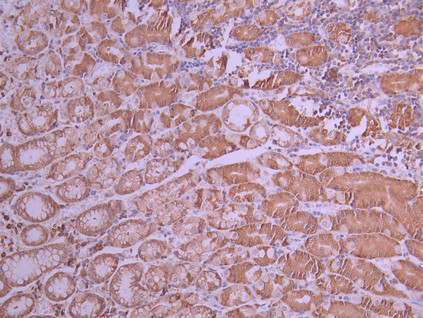

• IHC image of CSB-RA258376A0HU diluted at 1:100 and staining in paraffin-embedded human gastric cancer performed on a Leica BondTM system. After dewaxing and hydration, antigen retrieval was mediated by high pressure in a citrate buffer (pH 6.0). Section was blocked with 10% normal goat serum 30min at RT. Then primary antibody (1% BSA) was incubated at 4°C overnight. The primary is detected by a Goat anti-rabbit polymer IgG labeled by HRP and visualized using 0.05% DAB.